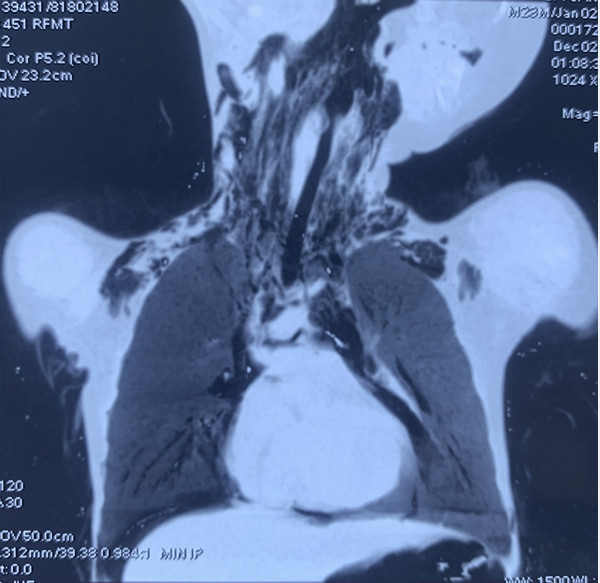

前不久,耳鼻咽喉头颈外科病院急诊收治一名外地转来的22月龄小男婴,据患儿家人讲,患儿2天前玩耍时突然出现哭闹,口唇发紫,气喘,夜间烦躁,不能入睡。在当地医院经抢救后检查胸部CT,提示气管隆突分叉处、左主支气管内异物;纵隔、颈部皮下多发积气,双侧少量气胸,考虑气管穿通伤。由于当地医疗技术及条件限制,患儿被紧急送往西安交大二附院救治。

耳鼻咽喉头颈外科病院接诊时,发现患儿精神差,口唇发紫,哭闹时伴有明显气促、喘息,听诊双肺干湿性啰音,右肺呼吸音低。家属无法提供准确异物误吸情况。值班医师接诊后结合患儿病史、体征及影像学检查结果,基本确诊“呼吸道异物、纵隔气肿、呼吸困难”,在行体格检查时,发现听诊与当地CT检查结果不符,重新做支气管CT三维重建扫描发现右主支气管有异物,说明异物在气管内存在移位、活动,这会加重呼吸困难,并随时会出现窒息,造成气管进一步损伤的风险也会增加。